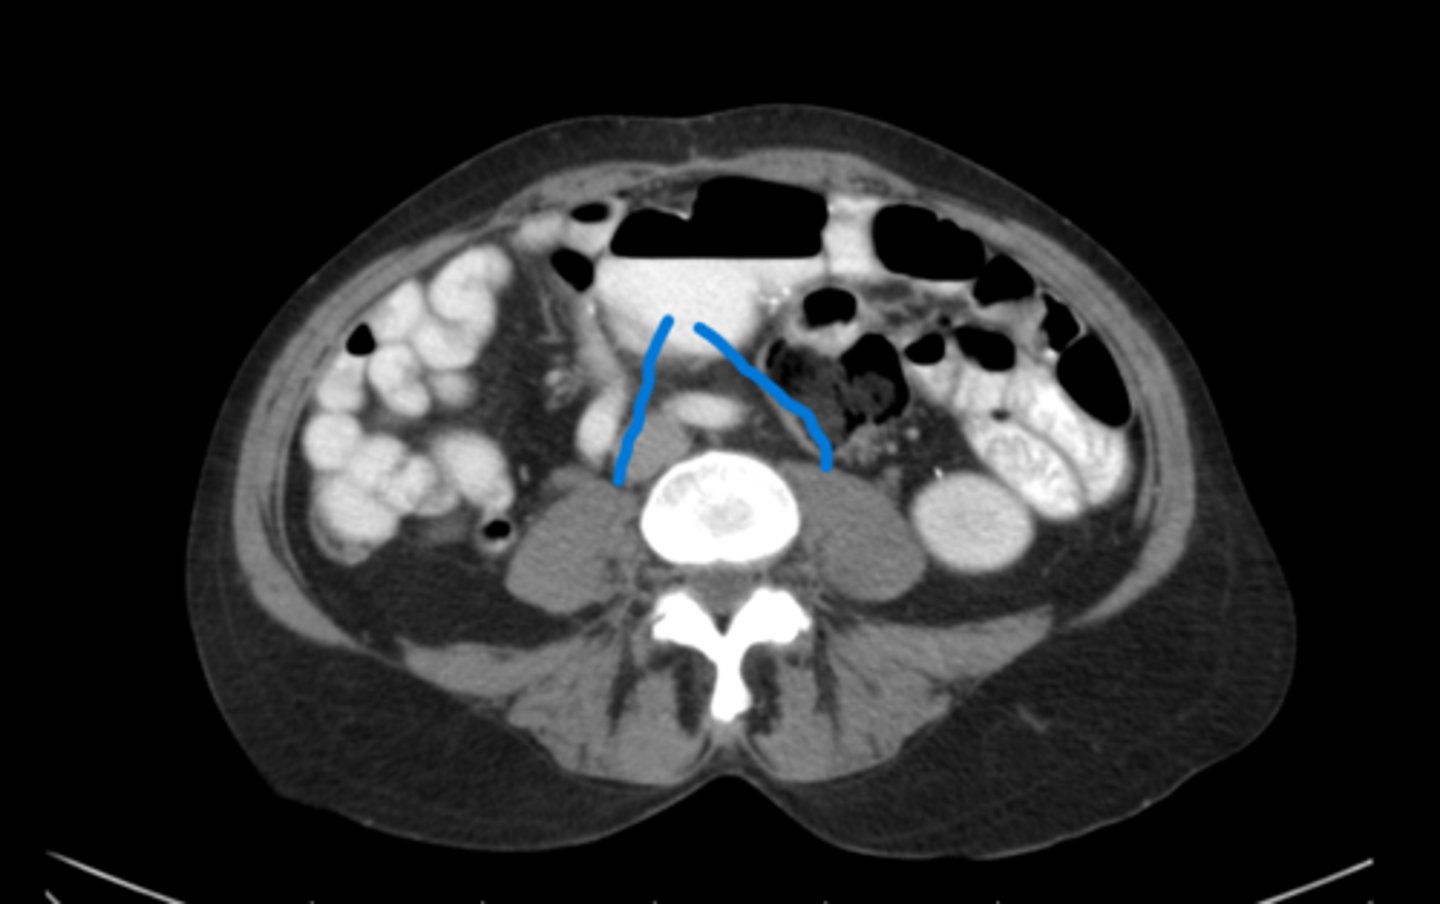

Psoas muscles

What are the red lines pointing to

L5 because of the bifurcation of the aorta

What vertebral level is this and how could you tell

The psoas muscles

What are the blue lines pointing to

Psoas muscles

What are the blue lines pointing to